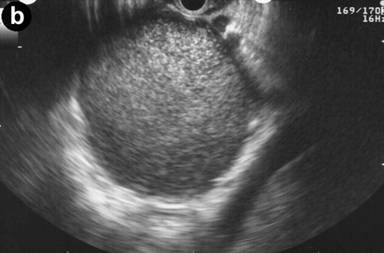

Figure 2. a. CT scan of the abdomen in a 56-year-old female with left upper quadrant pain demonstrates a unilocular pancreatic tail cyst. The cyst wall has variable thickness but does not demonstrate any nodularity. No solid mass was noted. Pseudocyst was suggested in the differential diagnosis of this lesion. b. EUS appearance of the same cyst in A. Thick mucoid cyst content appears granulated on ultrasound, but no visible septations or solid lesions demonstrated. c. Gross surgical resection specimen for the same patient (distal pancreatectomy with splenectomy). No malignancy was detected in this specimen. d. Photomicrograph of a mucinous cystadenoma (H&E, 400x). Columnar mucinous epithelial cells are seen overly ovarian stroma, which is a hallmark of these tumors. |